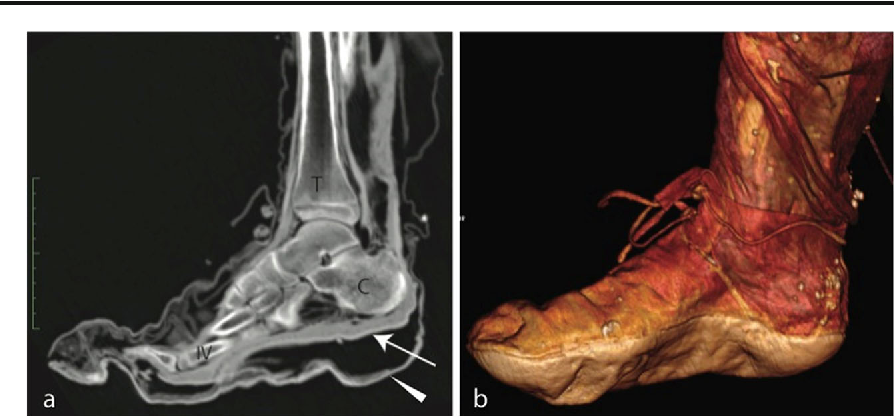

Achaemenid era shoes. Looking at numerous depictions, we could say this was the average footwear of most people. Of course footwear of king and royalty would have been more fancy in some ways

Achaemenid era shoes

I don't have a date for photo 1: could be post-Achaemenid